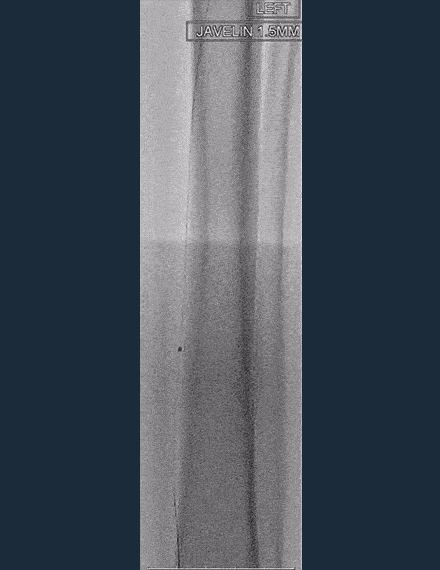

Shockwave Javelin Treatment

The lesion was wire crossable but not device crossable (IVUS did not cross). Shockwave Javelin Peripheral was able to advance through the lesion. -

Shockwave Javelin Peripheral was advanced via the posterior tibial artery and through the common plantar artery. -

120 pulses of Shockwave Javelin Peripheral delivered across the occluded lateral plantar and dorsalis pedis arteries. -